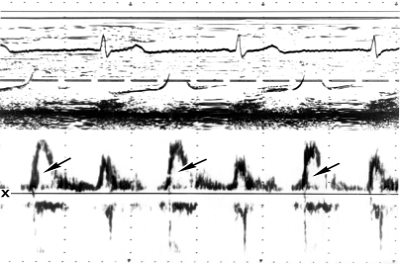

Рис. 9а). М-эхокардиограммы (вверху) и допплер-эхокардиограммы в форме спектрограмм (внизу) потока крови на уровне аортального клапана

В норме; отраженные сигналы от потока крови через аорту (указаны на спектрограмме стрелкой) возникают в систолу (следуют за желудочковым комплексом ЭКГ), направлены от изолинии х вниз (направление потока от датчика), имеют четкую очерченность и светлое «окно» в середине, что свидетельствует о ламинарном (нормальном) потоке.

Рис. 9б). М-эхокардиограммы (вверху) и допплер-эхокардиограммы в форме спектрограмм (внизу) потока крови на уровне аортального клапана: при стенозе устья аорты; отраженные сигналы от патологического потока крови через аорту (указаны стрелкой) регистрируются в виде сплошной заштрихованной полосы без «окна», что свидетельствует о турбулентном потоке, не имеют четкой очерченности и направлены как вниз, так и вверх от изолинии из-за направления части вихревых потоков к датчику